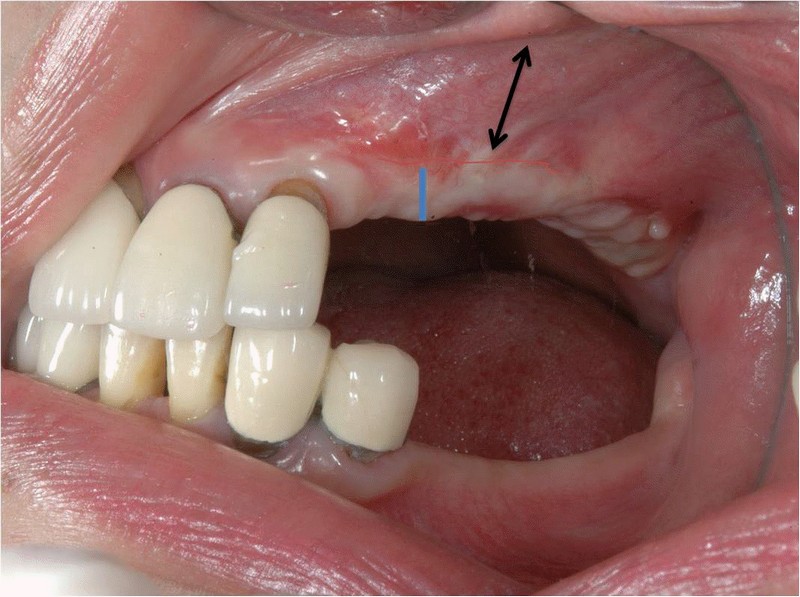

牙齦移植術(補肉)